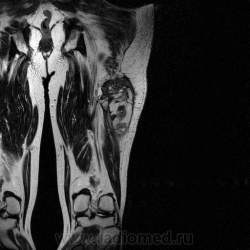

Ну вот аксиальные срезы, где то затерял =(

С учетом вашего опыта, мне кажется Вам и без дословной интерпретации МР-протокола будет все понятно.

Мой коллега в заключении указал о вероятней всего рабдолейомиосаркоме, если я ошибся то чуть позже поправлюсь.

Я тоже пока что в этом деле лось, но думаю дело поправимое, на днях улетаю С-Петербуг в МАПО(цикл КТ и МРТ), ну да ладно, что косается пациента то он ещё в 2007 году обращался по месту жительства к травматологу по поводу ушиба бедра с формированием гематомы, была назначена местная рассасывающая терапия, до 2009г. видимо ждали пока рассасется в декабре обратился к хирургу по поводу посинения и увеличения в объёме задней поверхности бедра, назначен гепарин в феврале был вскрыт абсцесс в этом месте, далее только в марте сподхватились по УЗИ-мягких тканей признаки образования, ну и открытая ножевая биопсия: Описание изменений, выявленных при микроскопическом исследовании: в материале фрагменты опухоли, представленной пучками вытянутых клеток с полиморфными гиперхромными, местами уродливыми ядрами. Определяется значительное количество митозов, встречаются поля некроза опухоли. При иммуногистохимическом исследовании опухолевые клетки экспрессируют виментин, отсутствует реакция на десмин, гладко-мышечный актин, S100. Патоморфологическое заключение: саркома мягких тканей, боее вероятно фибросаркома.